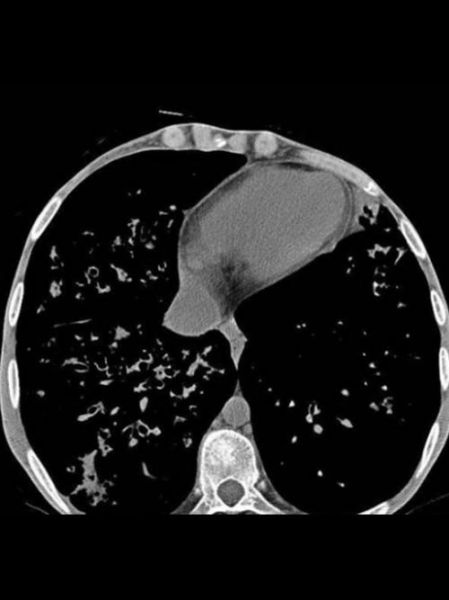

囊性纤维化(Cystic Fibrosis,CF)是一种常染色体隐性遗传病,由CFTR基因突变导致氯离子通道功能障碍,进而引发多系统黏液堵塞。患者最常问的两个问题是:“囊性纤维化能治好吗?”以及“现在有哪些最新治疗进展?”下面分板块拆解。

目前医学共识:囊性纤维化仍无法彻底根治,但已从“儿童期致命病”转变为“可控慢病”。

• 平均生存期从上世纪60年代的10岁提升至40岁以上(欧美数据)。

• “治愈”定义正在变化:把肺功能长期维持在正常下限、减少住院次数,即视为临床治愈。